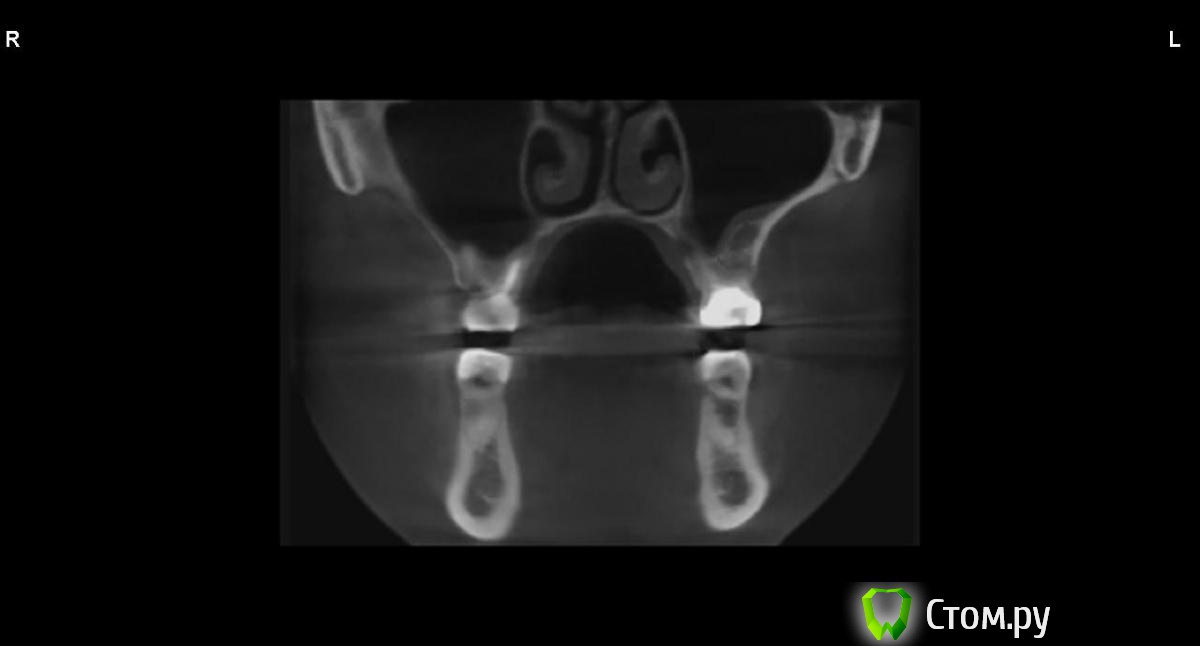

jm3300 Опубликовано 9 сентября, 2014 Автор Поделиться Опубликовано 9 сентября, 2014 вот, набросал Ссылка на комментарий

АнтонТЛТ Опубликовано 9 сентября, 2014 Поделиться Опубликовано 9 сентября, 2014 (изменено) это нижняя носовая раковина, возможно Изменено 9 сентября, 2014 пользователем АнтонТЛТ Ссылка на комментарий

АнтонТЛТ Опубликовано 9 сентября, 2014 Поделиться Опубликовано 9 сентября, 2014 я понял что это)))это артефакт от зуба, обратите внимание на правую сторону, там в пазухе тоже зуб есть, после эндодонтии)) Ссылка на комментарий